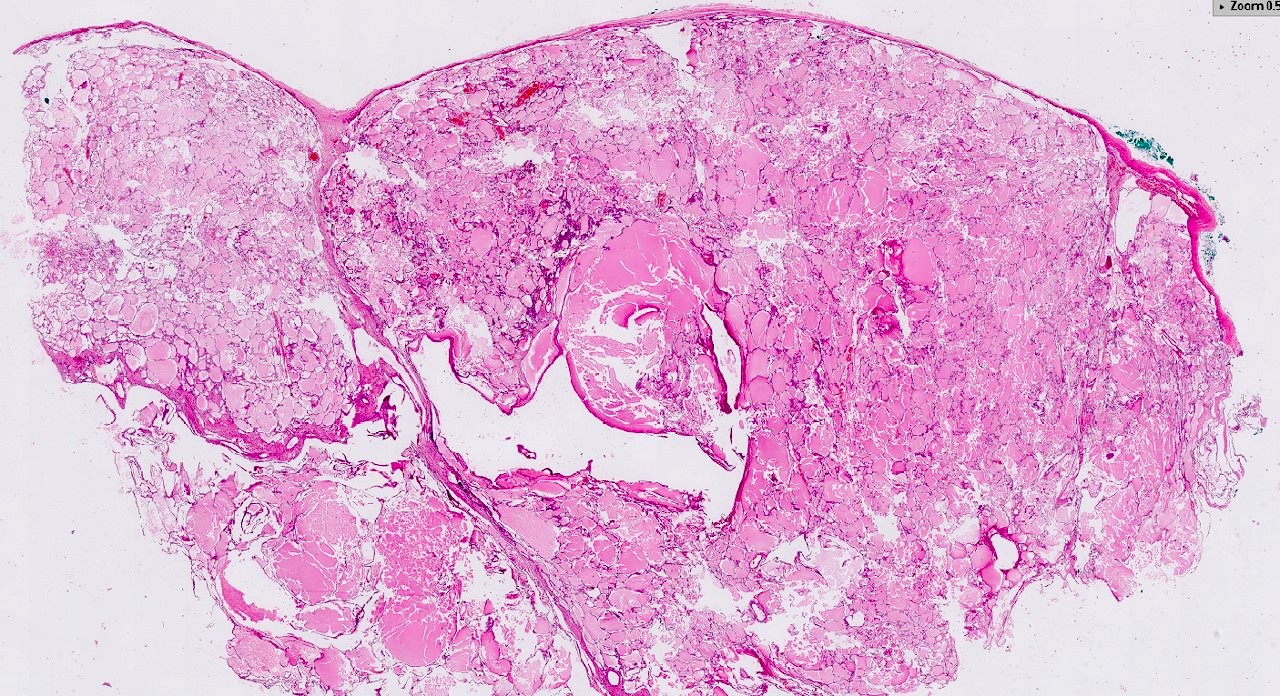

Microscopic (histologic) description

- Cysts lined with flat / cuboidal / hobnail cells (or are denuded)

- Epithelial elements consist mainly of mature and immature / abortive tubules and small papillae resembling immature glomeruli

- Key histological findings of the variably cellular septa include

- Nephroblastomatous epithelial elements

- Islands of undifferentiated blastema and differentiated mesenchymal elements (skeletal muscle and less often cartilage and fat) (J Urol 2010;183:1585)

- Focally, the septal elements may protrude into the cystic spaces in microscopic papillary folds

Microscopic (histologic) images

Contributed by Americo Brilhante, M.D. and Daniel Athanazio, M.D., Ph.D.